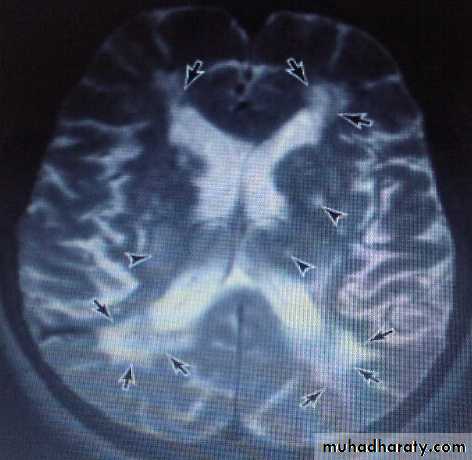

The MRI in multi-infarct dementia may show multiple large cortical or small subcortical lacuncies.

Extensive areas of low density in subcortical white matter are seen in Binswanger disease (subcortical arteriosclerotic encephalopathy), which may be a related condition but with insidious onset & slowly progression, features that distinguish it from multi-infarct dementia, though some patients show stepwise progression.

MRI is more sensitive than CT for detecting these abnormalities.

VASCULAR DEMENTIA due to chronic hypertention